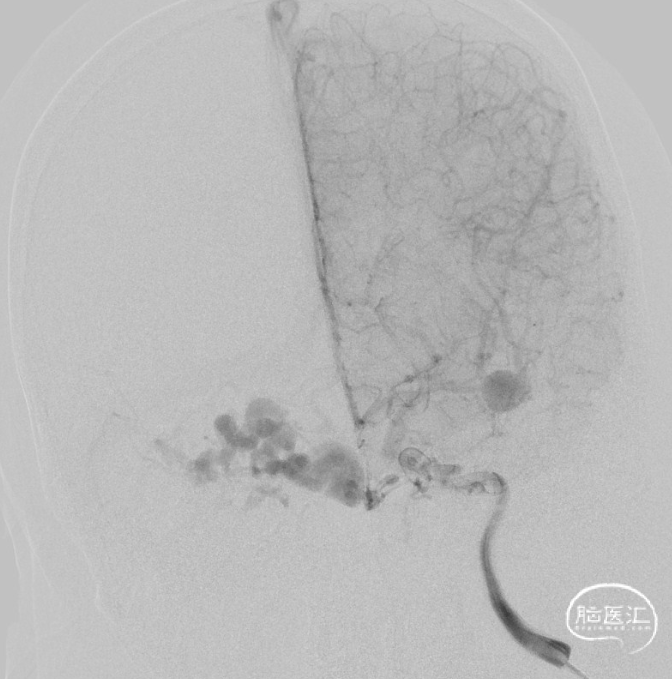

一期治疗

治疗经过